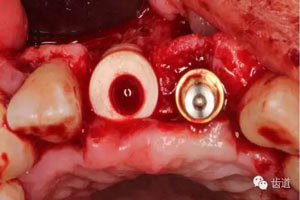

種植手術:

![].jpg ].jpg](/UploadFiles/FCK/2015-12/6358588061074816647618673.jpg)